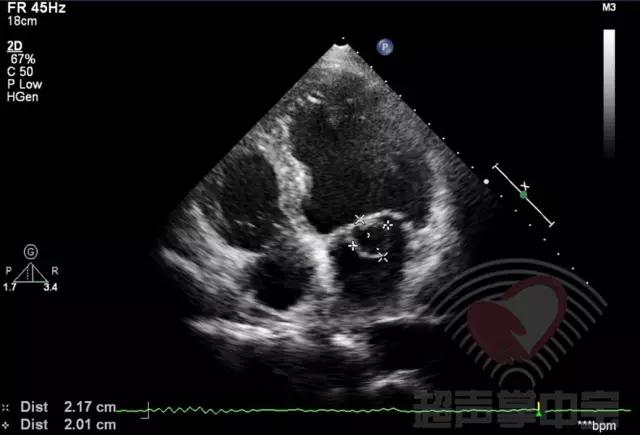

经典病例▏二尖瓣囊肿中竟然全是血液? 图1:心尖四腔心切面显示二尖瓣前叶增厚,前叶左房面可见一囊袋状物附着,大小2.01×2.17cm,囊壁完整,其内透声良好